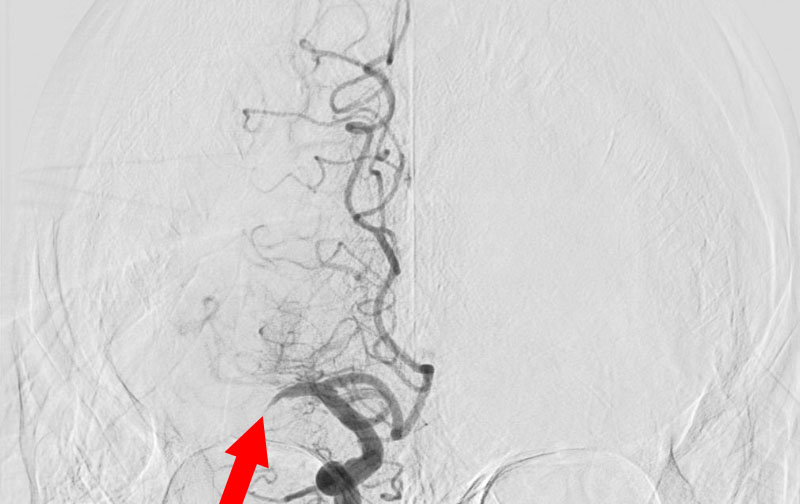

1607

'26年1月8日

脳梗塞・急性期

70代

救急外来

'26年1月